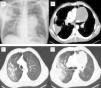

(A) Chest radiography: heterogeneous infiltration in the right upper lobe and homogeneous opacity in the left hilar region. (B)–(D) Chest Computed Tomography of the thorax: hypodense mass of 9cm with well defined margins located in the mediastinum with extension to the left upper lobe, areas of consolidation in the right upper lobe associated with micro-nodular infiltration and ground-glass opacities.

Herein the authors described the case of a 50-year-old male patient, Caucasian, smoker. As a background he had arterial hypertension and discoid lupus erythematosus. His usual medication was candesartan 16mg, deflazacort 3mg/day and chloroquine 250mg/day. He presented in our hospital complaining of dyspnea, cough, asthenia and weight loss with three weeks evolution. His physical exam was unremarkable, except for malar and cervical cutaneous rash related to his discoid lupus. Chest X-ray and computed tomography showed pulmonary infiltrations in the right upper lobe and a mediastinic mass of 9cm (Fig. 1). Abdominal CT did not show any abnormalities. Sputum analysis confirmed a diagnosis of pulmonary tuberculosis and the patient started anti-tuberculosis treatment. His HIV and hepatitis virus status were negative. Bronchoalveolar samples were negative for malignancy and CT-guided transthoracic core biopsy of the mediastinal mass only showed necrotic tissue, so the patient underwent a surgical lung biopsy.